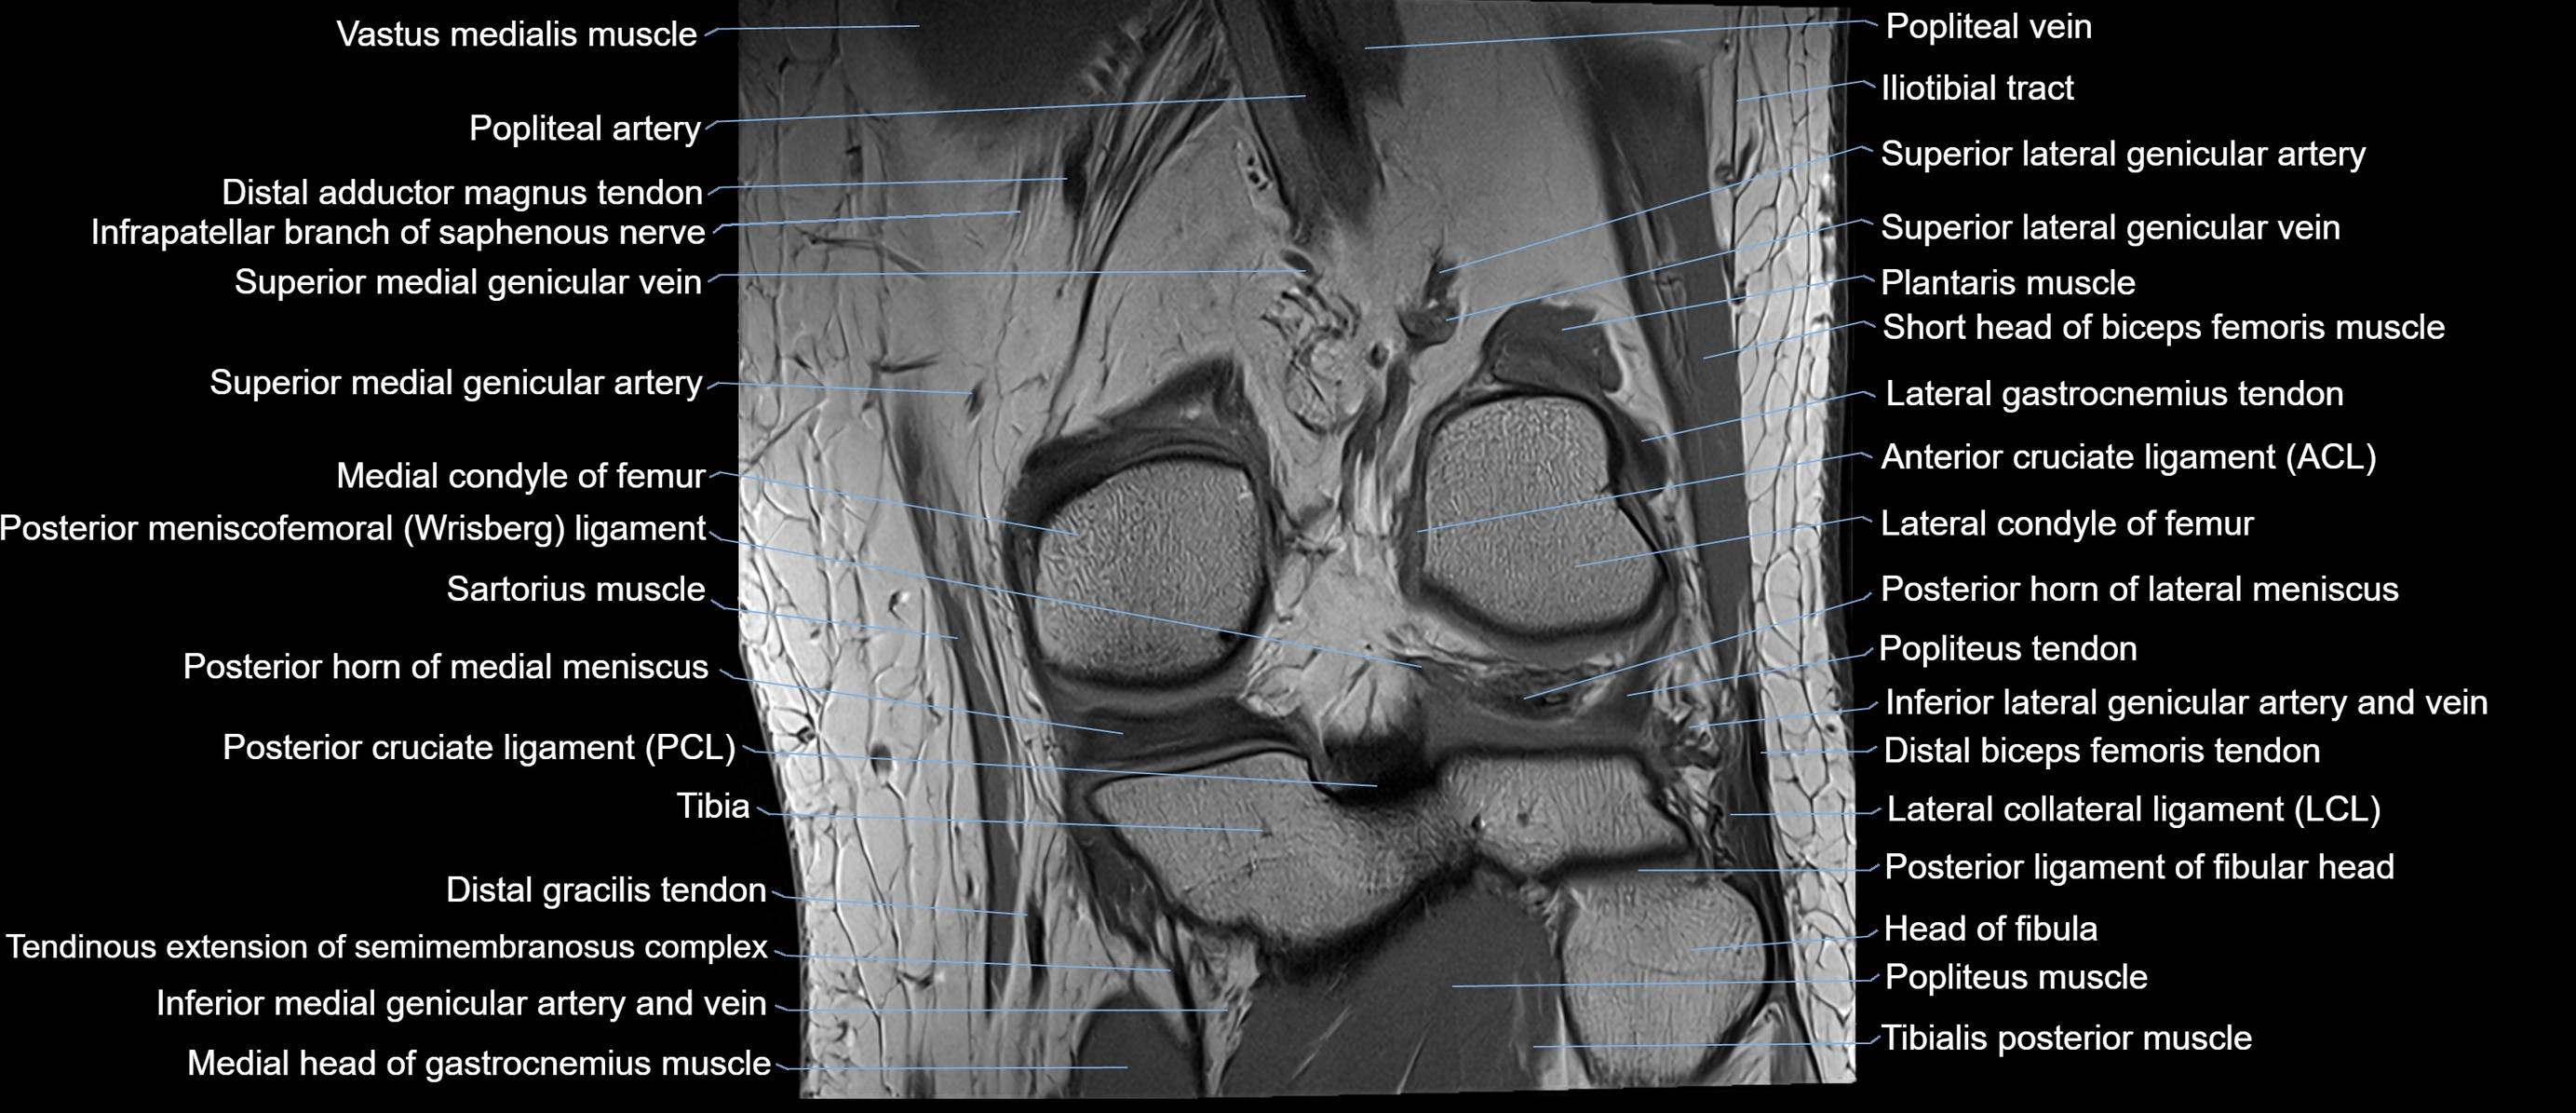

- Posterior cruciate ligament

- Posterior horn of lateral meniscus

- Posterior horn of medial meniscus

- Posterior meniscofemoral ligament